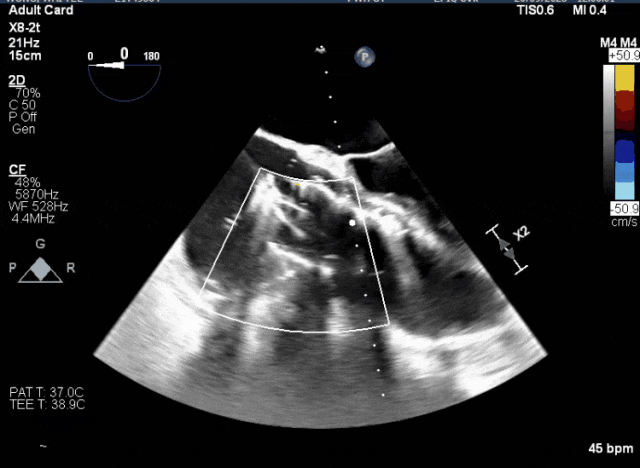

術(shù)前超聲顯示三尖瓣重度反流合并拴系

術(shù)中TEE成像困難,偽影干擾

術(shù)中TEE觀察夾持件的位置